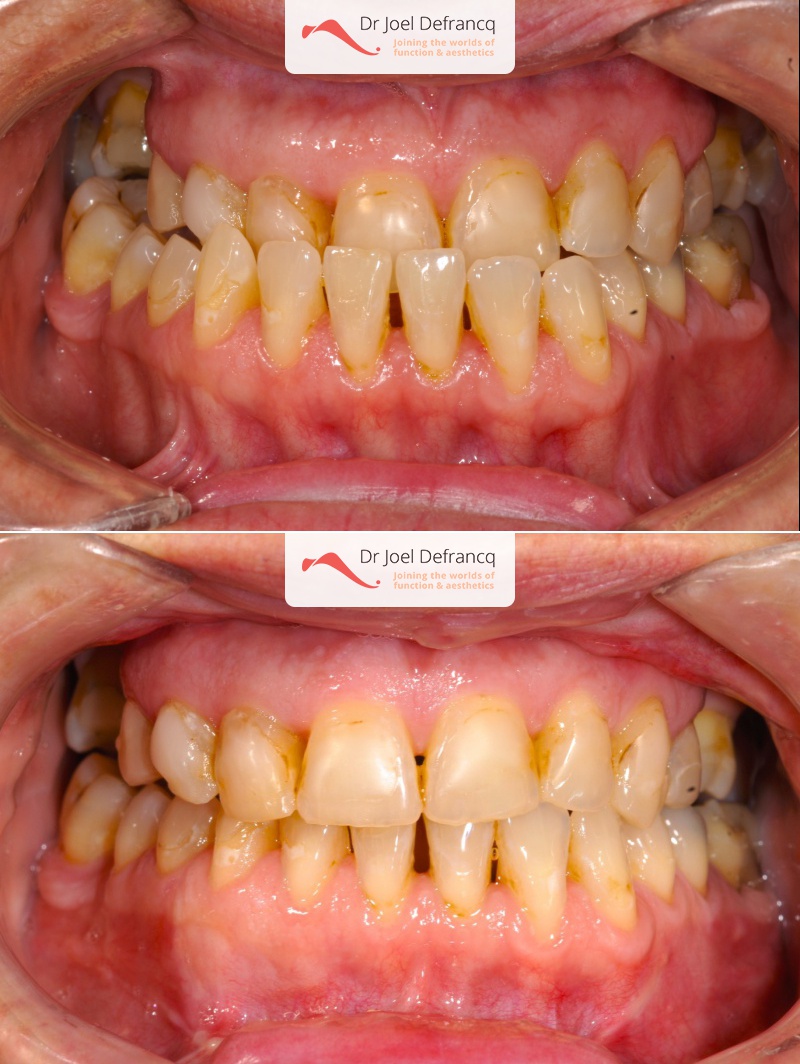

Doria: Te grote onderkaak, te kleine bovenkaak

Diagnose van het gezicht

- Te grote onderkaak (Onderbeet)

- Te kleine bovenkaak